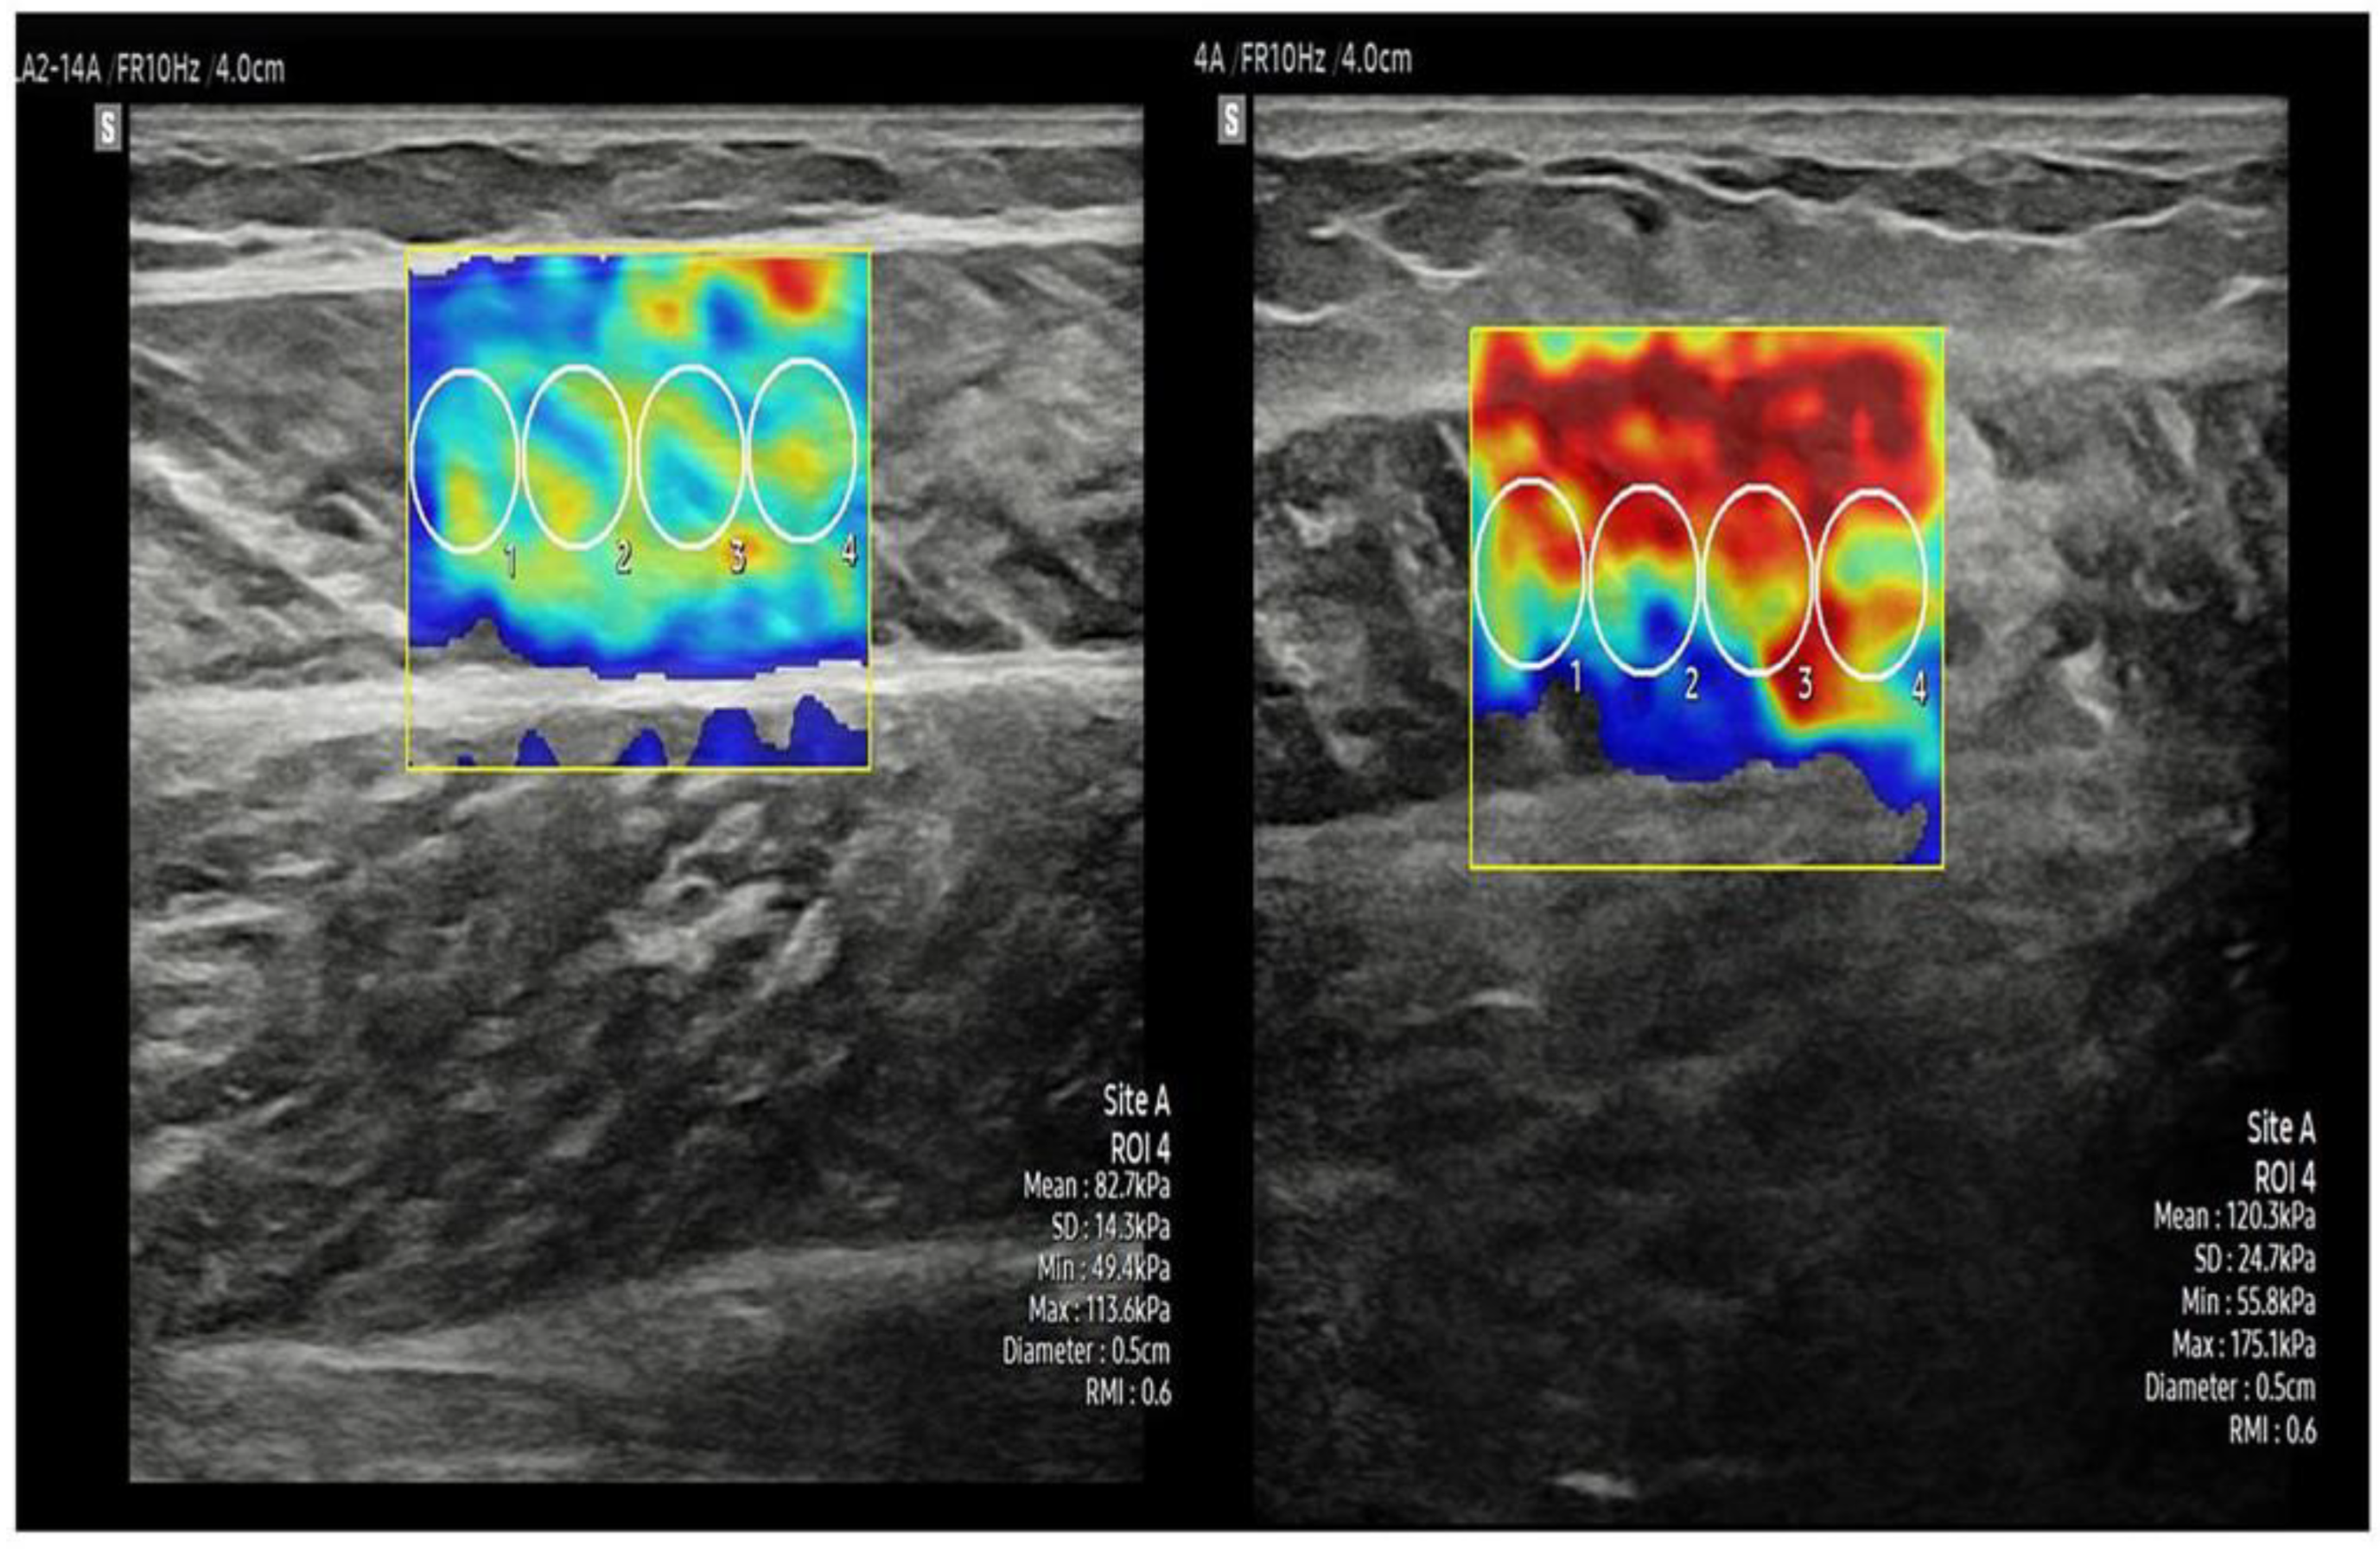

2.3.4. Stiffness and Thickness of the Muscle

- Lee, Y.; Kim, M.; Lee, H. The measurement of stiffness for major muscles with shear wave elastography and myoton: A quantitative analysis study. Diagnostics 2021, 11, 524. [Google Scholar] [CrossRef] [PubMed]